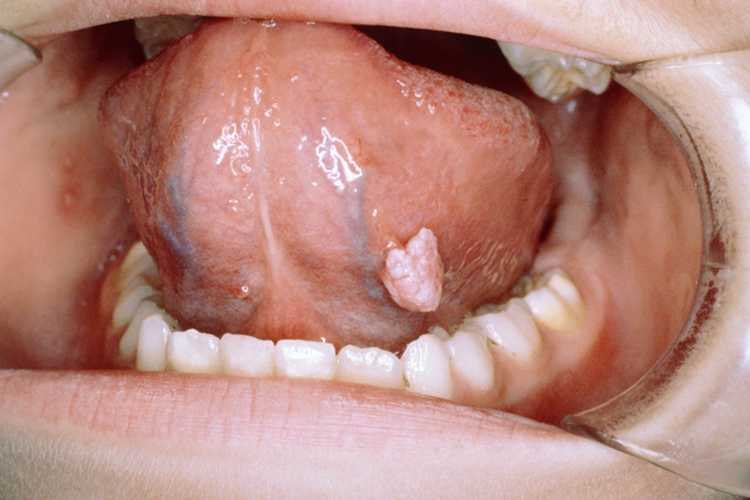

乳头状瘤是按肿瘤形态命名的一种良性肿瘤,呈圆形或椭圆形,形似乳头,来源于上皮组织,病因尚不十分明确。

乳头状瘤为上皮来源的肿瘤,多为良性。病理表现为上皮组织高度增生,鳞状上皮向外过度生长形成乳头,乳头呈圆形或椭圆形上皮团块,中心有疏松而富有脉管的结缔组织。